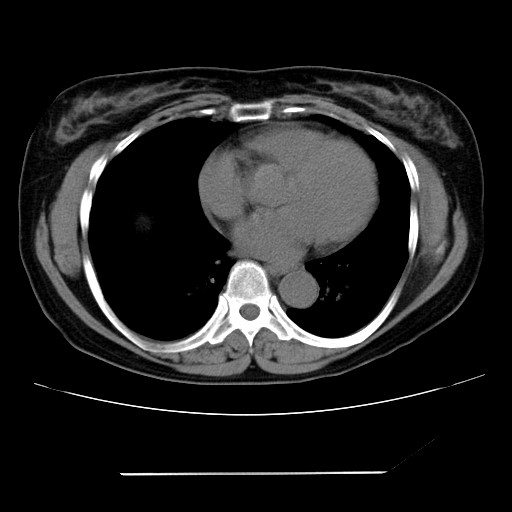

标题: CT24018:女性,62岁,咳嗽4年,无热,胸部CT扫 [打印本页]

女性,62岁,长期咳嗽,既往从事工作有粉尘接触,有高血压病史,110/150mmhg,近日咳嗽加重,脸面浮肿,请大家帮看下,

1、尘肺;2、慢性支气管炎合并肺部感染;3、心影增大(左房、左室大),考虑高血压性心脏病。

能否考虑是尘肺引起的肺源性心脏病?

慢支并肺部炎症;右肺结核球?主肺动脉、右肺动脉影不宽,右心室不大,不支持肺心病;无心包积液。